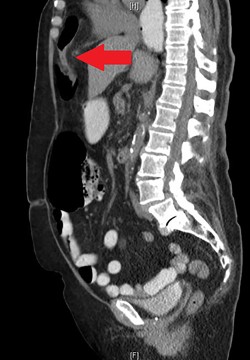

During the hospitalization, initial cardiac workup with 12-lead electrocardiogram and serial troponins was negative. The patient’s oncologic medications were held without improvement of the pain as well as to prevent leukopenia and neutropenia, if surgery was indicated. Palliative care was unable to achieve adequate pain control with oral and IV medications, and the patient did not want to pursue hospice care. Surgical consultation was obtained, and further evaluation with a CT scan of the chest, abdomen and pelvis with oral and IV contrast demonstrated an anteromedial diaphragmatic defect through which a prominent amount of mesenteric fat and a portion of the colon herniated representing a Morgagni hernia (Figs. 1–4). An increase in the size of the previously known PEH as well as the Morgagni hernia was noted. Due to continued chest pain unrelieved by opioids, a joint decision was made between surgeon, oncologist and the patient to proceed with surgery. She underwent successful robotic laparoscopic repair of the Morgagni hernia and PEH with dulex mesh for reinforcement. Her chest pain subsequently resolved. The patient gradually tolerated oral feeds and was eventually discharged in stable condition.

A sagittal view from the 2017 CT chest, abdomen and pelvis with IV and PO contrast demonstrates the Morgagni hernia with fat sweeping up through the diaphragmatic defect (red arrow) and a retrocardiac paraesophageal hernia (blue arrow).